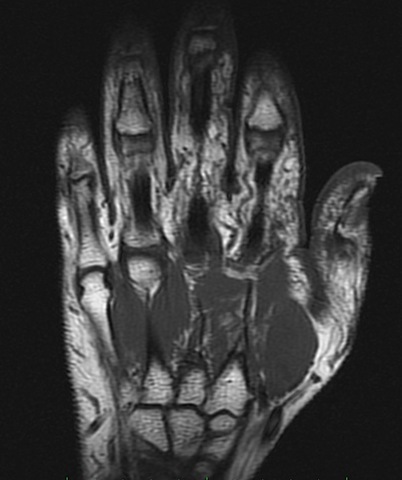

• Anatomia humana

Anatomia humana

Mansfield y A.A. Maudsley en 1977 publicaron la primera imagen

seccional de una región de la anatomía humana, un

dedo. Doble hélice del DNA.

Los hallazgos de Mansfield y Lauterbur y del

mismo Damadian aceleraron el desarrollo de la técnica.

En 1977, W. Hinshaw et al. publicaron imágenes de

RM de la muñeca, R. Damadian logró reconstruir la

imagen del tórax y P. Mansfield desarrolló las secuencias

EPI. R. C. Hawkes y Moore et al en 1980 obtuvieron

las primeras imágenes de la cabeza